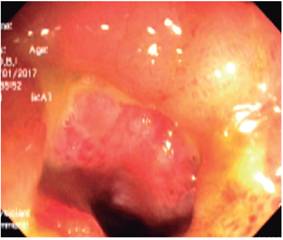

La colonoscopia de control se realizó el 10 de enero 2017 y se encontró úlcera circunferencial en válvula ileocecal con severo edema, eritema, congestión (estenosis inflamatoria severa), con úlceras en el íleon distal; se tomaron múltiples biopsias (Figura 1) y se hospitalizó con alta sospecha de EC estenosante. En las biopsias se evidenció mucosa ulcerada constituida por un estroma de tejido fibroconectivo vascularizado con marcados cambios inflamatorios, alteración arquitectural focal caracterizada por aplanamiento de vellosidades y borde en cepillo conservado con esfacelo. Se encontró un denso infiltrado linfoplasmocitario con agregados linfoides, criptas atróficas y pérdida de células caliciformes sin evidencia de parásitos, granulomas, ni cambios displásicos.